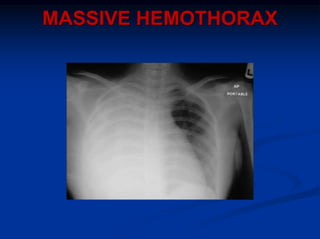

MASSIVE HEMOTHORAX

>1500ml blood in chest cavity, or

<1500ml initially, but 200ml/h for 2-4hr

Signs; shock, absence breath sounds +/- dullness percussion on

one side chest, ventilatory embarrassment, shift mediastinum

Management; restoration blood volume (crystalloids +

blood/autotransfusion), decompression chest cavity (#38F ICC

5th ICS) – may need to clamp tube and consider autotransfusion

Do not wait for CXR to confirm diagnosis

Indication for urgent thoracotomy, esp. if ongoing

transfusion requirements

85% cases due to injured systemic vessel; intercostal or internal

mammary artery, less commonly hilum of lung or myocardium

15% cases due to deep pulmonary lacerations – treated by

oversewing or resection segment or lobe

Beware penetrating wounds medial to nipple anteriorly, or

scapula posteriorly as may require ER or urgent thoracotomy for

possible damage to great vessels, hilar structures, or heart, with

potential for cardiac tamponade